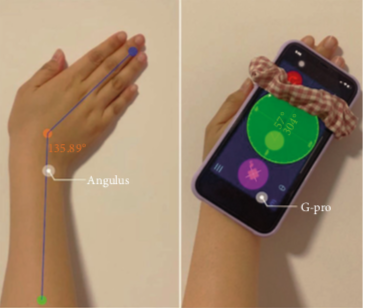

腕部远端桡尺关节测试

腕部 DRUJ 球拍测试远侧桡尺关节球拍测试的可靠性和有效性分析 Nagashima, M., Omokawa, S., Hasegawa, H., Nakanishi, Y., Kawamura, ...